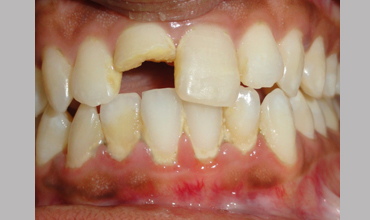

Management Of Fractured Tooth With Cast Post & Core